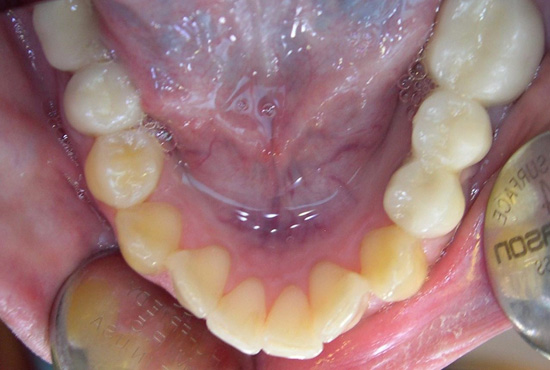

Case 2 - Lower Teeth Before

Case 2 - Lower Teeth After